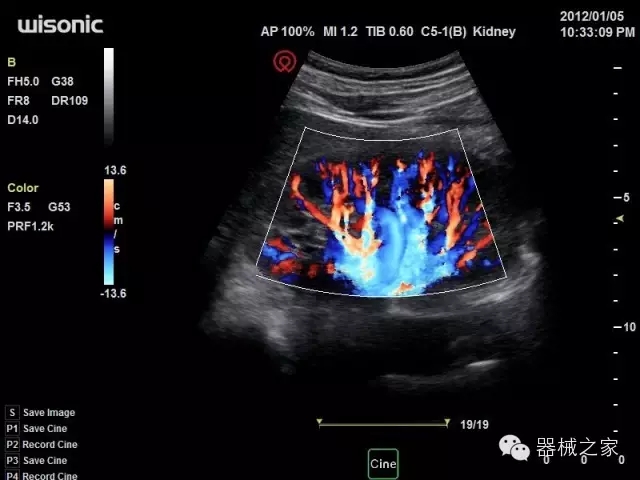

經(jīng)典產(chǎn)品:S8EXP

臨床圖片賞析

產(chǎn)品特點

優(yōu)異的成像技術(shù)

·亞陣元技術(shù):獨有的亞陣元技術(shù),對獨立晶片做二次切割,減少旁瓣偽像,增加臨床診斷的準(zhǔn)確性;

·μ-Scan微米成像技術(shù):開立獨有的μ-Scan技術(shù),還原出真實細(xì)膩、層次對比優(yōu)異的二維圖像;

·倒相諧波成像技術(shù):倒相諧波技術(shù)在去除基波信號的基礎(chǔ)上獲取兩倍二次諧波信號,提高組織圖像的對比分辨力;

·智能微血流成像技術(shù):智能微血流捕捉技術(shù)可以提取出隱藏在背景噪聲中的弱血流信號,大大提高低速血流的敏感性;

全面的臨床解決方案

超聲科常規(guī)領(lǐng)域應(yīng)用

·移植S40高端臺式彩超高端平臺技術(shù),滿足超聲科腹部、淺表、婦產(chǎn)科、心血管、肌骨等應(yīng)用,提供超聲科完美解決方案;

·實時的彈性成像技術(shù):提高了小器管(乳腺,甲狀腺、淺表軟組織腫瘤等)疾病鑒別診斷;

·IMT血管內(nèi)中膜自動測量:為血管性疾病評估提供了有效的評估手段;

·心功能綜合指數(shù)(TEI指數(shù)):用于左、右心室整體心臟收縮舒張功能評估的測量方法;

·全方位可調(diào)M型:有利于更好的觀察心腔大小及室壁階段性運動的異常情況;

·組織多普勒成像(TDI):TDI可定量評價心肌運動,判斷是否有局部病變,還可評價早期的舒張功能;

·高效3D/4D成像技術(shù):高速的4D幀頻,豐富的3D成像模式,智能斷層切片功能;

POC領(lǐng)域解決方案

·外觀小巧;

·穿刺增強技術(shù):可有效提高進(jìn)針區(qū)圖像分辨率,提高進(jìn)針亮度,全面提高一次性穿刺的成功率;

全面的術(shù)中探頭解決方案

·小凸探頭:開放性手術(shù),實時監(jiān)測病灶位置,提高手術(shù)成功率,可應(yīng)用于麻醉科、肝膽外科、腫瘤外科、神經(jīng)外科、泌尿外科等手術(shù);

·L型線陣探頭:高分辨率圖像,清晰顯示病灶位置,提高手術(shù)成功率,可應(yīng)用于麻醉科、胸外科、肝膽外科、腫瘤外科、神經(jīng)外科、泌尿外科等應(yīng)用;

·MPTEE:經(jīng)食道探頭術(shù)中監(jiān)測,可測量心臟前負(fù)荷(左室舒張末期大小、右房大?。?、心排血量、后負(fù)荷、收縮功能、室壁運動分析、肝靜脈血流(與中心靜脈壓相關(guān))等,術(shù)后還能及時評估手術(shù)效果評估;

·獨有的大角度及實時溫控技術(shù),能同一切面顯示宮頸及宮體,有效減低了患者的痛苦,及保護(hù)粘膜保證了醫(yī)療安全;

高效的人機(jī)工程學(xué)設(shè)計

·15‘’高清醫(yī)用顯示器;

·內(nèi)置雙探頭接口;

·可升降臺車,1拖3探頭擴(kuò)展器;

·m-Tuning一鍵優(yōu)化;